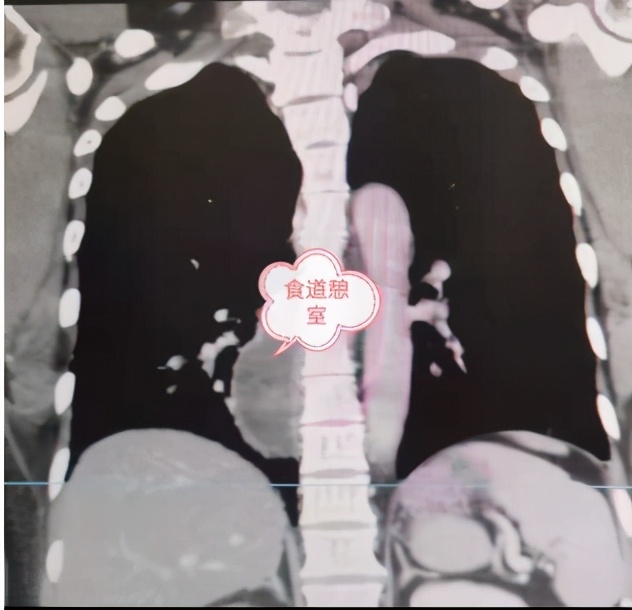

患者耿某,女,46岁,盘州市松河乡人,1个月前无明显诱因出现进食后胸部疼痛,为阵发性烧灼样疼痛,到该院心胸泌尿外科住院治疗。据悉,耿某一年前接受过纵膈肿瘤切除手术。住院期间完善胸腹部CT、胃镜、食道造影检查,明确诊断为“食道下段憩室”。

该科副主任王森介绍道:“食道憩室是在日常生活中比较常见的一种疾病。它通常都是由于食管壁局限性囊状外突,主要症状为吞咽困难和食物返流,是常见的食管良性疾病,但可继发感染、穿孔、恶变。食管下段憩室大多位于近膈上处,多数是由于食管部位发生一些损伤或者食管裂口疝的形成导致的,期间会伴有吞咽困难,腹部疼痛,并且有一些恶臭的味道,轻微的情况是可以不用治疗的,如果下段憩室比较严重,需要考虑手术治疗的办法。”

本次手术由该院副院长付强主刀,该科团队配合实施完成。手术过程分两步:首先,取左胸后外侧切口沿第七肋上缘进胸,探查见食管下段憩室大小为7cmX4cm,充分分离后切除;而后行食管与胃部进行吻合重建术,术中出血较少,患者各生命体征均正常,手术历时5个小时,非常成功。术后,在医护人员的精心护理和治疗下,耿某恢复良好。